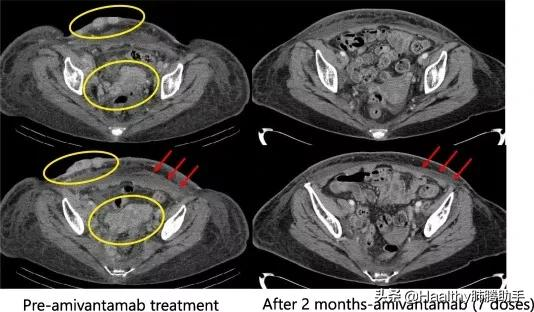

影像學檢查顯示:Amivantamab治療 2 個月後皮下轉移和融合的盆腔和腹股溝淋巴結幾乎消退,左側胸腔積液減少。